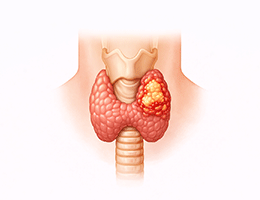

갑상선암 (Thyroid Cancer)